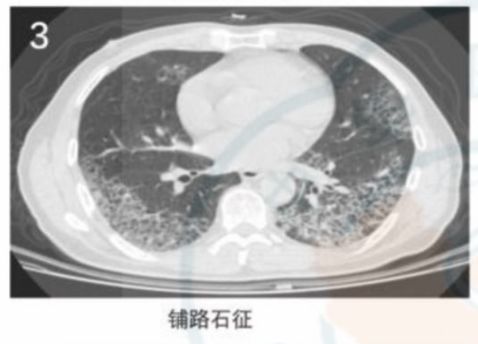

很多疾病都会引起小叶内间隔增厚,最常见的是各种间质性肺炎。间质性肺炎常有其他间质性改变,临床上大多数起病缓慢,不像新冠肺炎那么急骤,常无发热,鉴别一般不难。一般的肺炎很少有小叶内间隔增厚。所以,小叶内间隔增厚对诊断新冠肺炎价值较大。小叶内间隔增厚在CT上表现为细小的网格状阴影,甚至铺路石征。

仔细看CT,你会发现新冠肺炎的磨玻璃、斑片状阴影内常有细小的网格状阴影。

再来看这个新冠肺炎患者,磨玻璃阴影内有清晰的网格状阴影,类似铺路石征。

图9